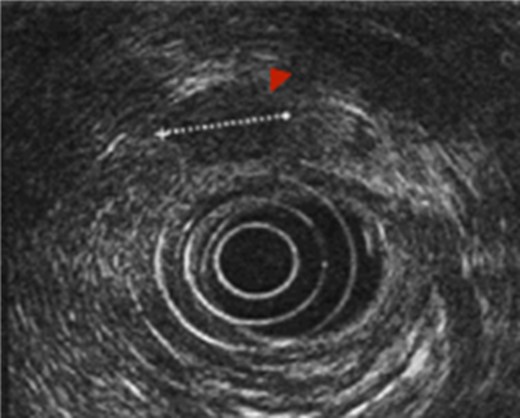

First the abdominal ultra sonography (AUS) and then CT scan revealed the presence of well-defined hypodense pancreatic head mass of 2 cm of diameter, determining bile duct and Wirsung’s duct dilatation; mesenteric vessels were clearly free of infiltration, no liver or lung suspected lesions were detected as well as volume increased lymph nodes (Fig. 1). Ecoendoscopic ultra sonography (EUS) confirmed the presence of a hypoechoic and well-defined pancreatic head mass (18 × 15 mm) and without sign of vessels infiltration (Fig. 2). A fine-needle aspiration (FNA) was performed and histopathological examination showed the presence of neoplastic cells with morphological features like the lung ones and consistent with metastasis from primary adamantinoma.

EUS. EUS confirmed the presence of a hypoechoic and well-defined mass of diameter 18 × 15 mm.